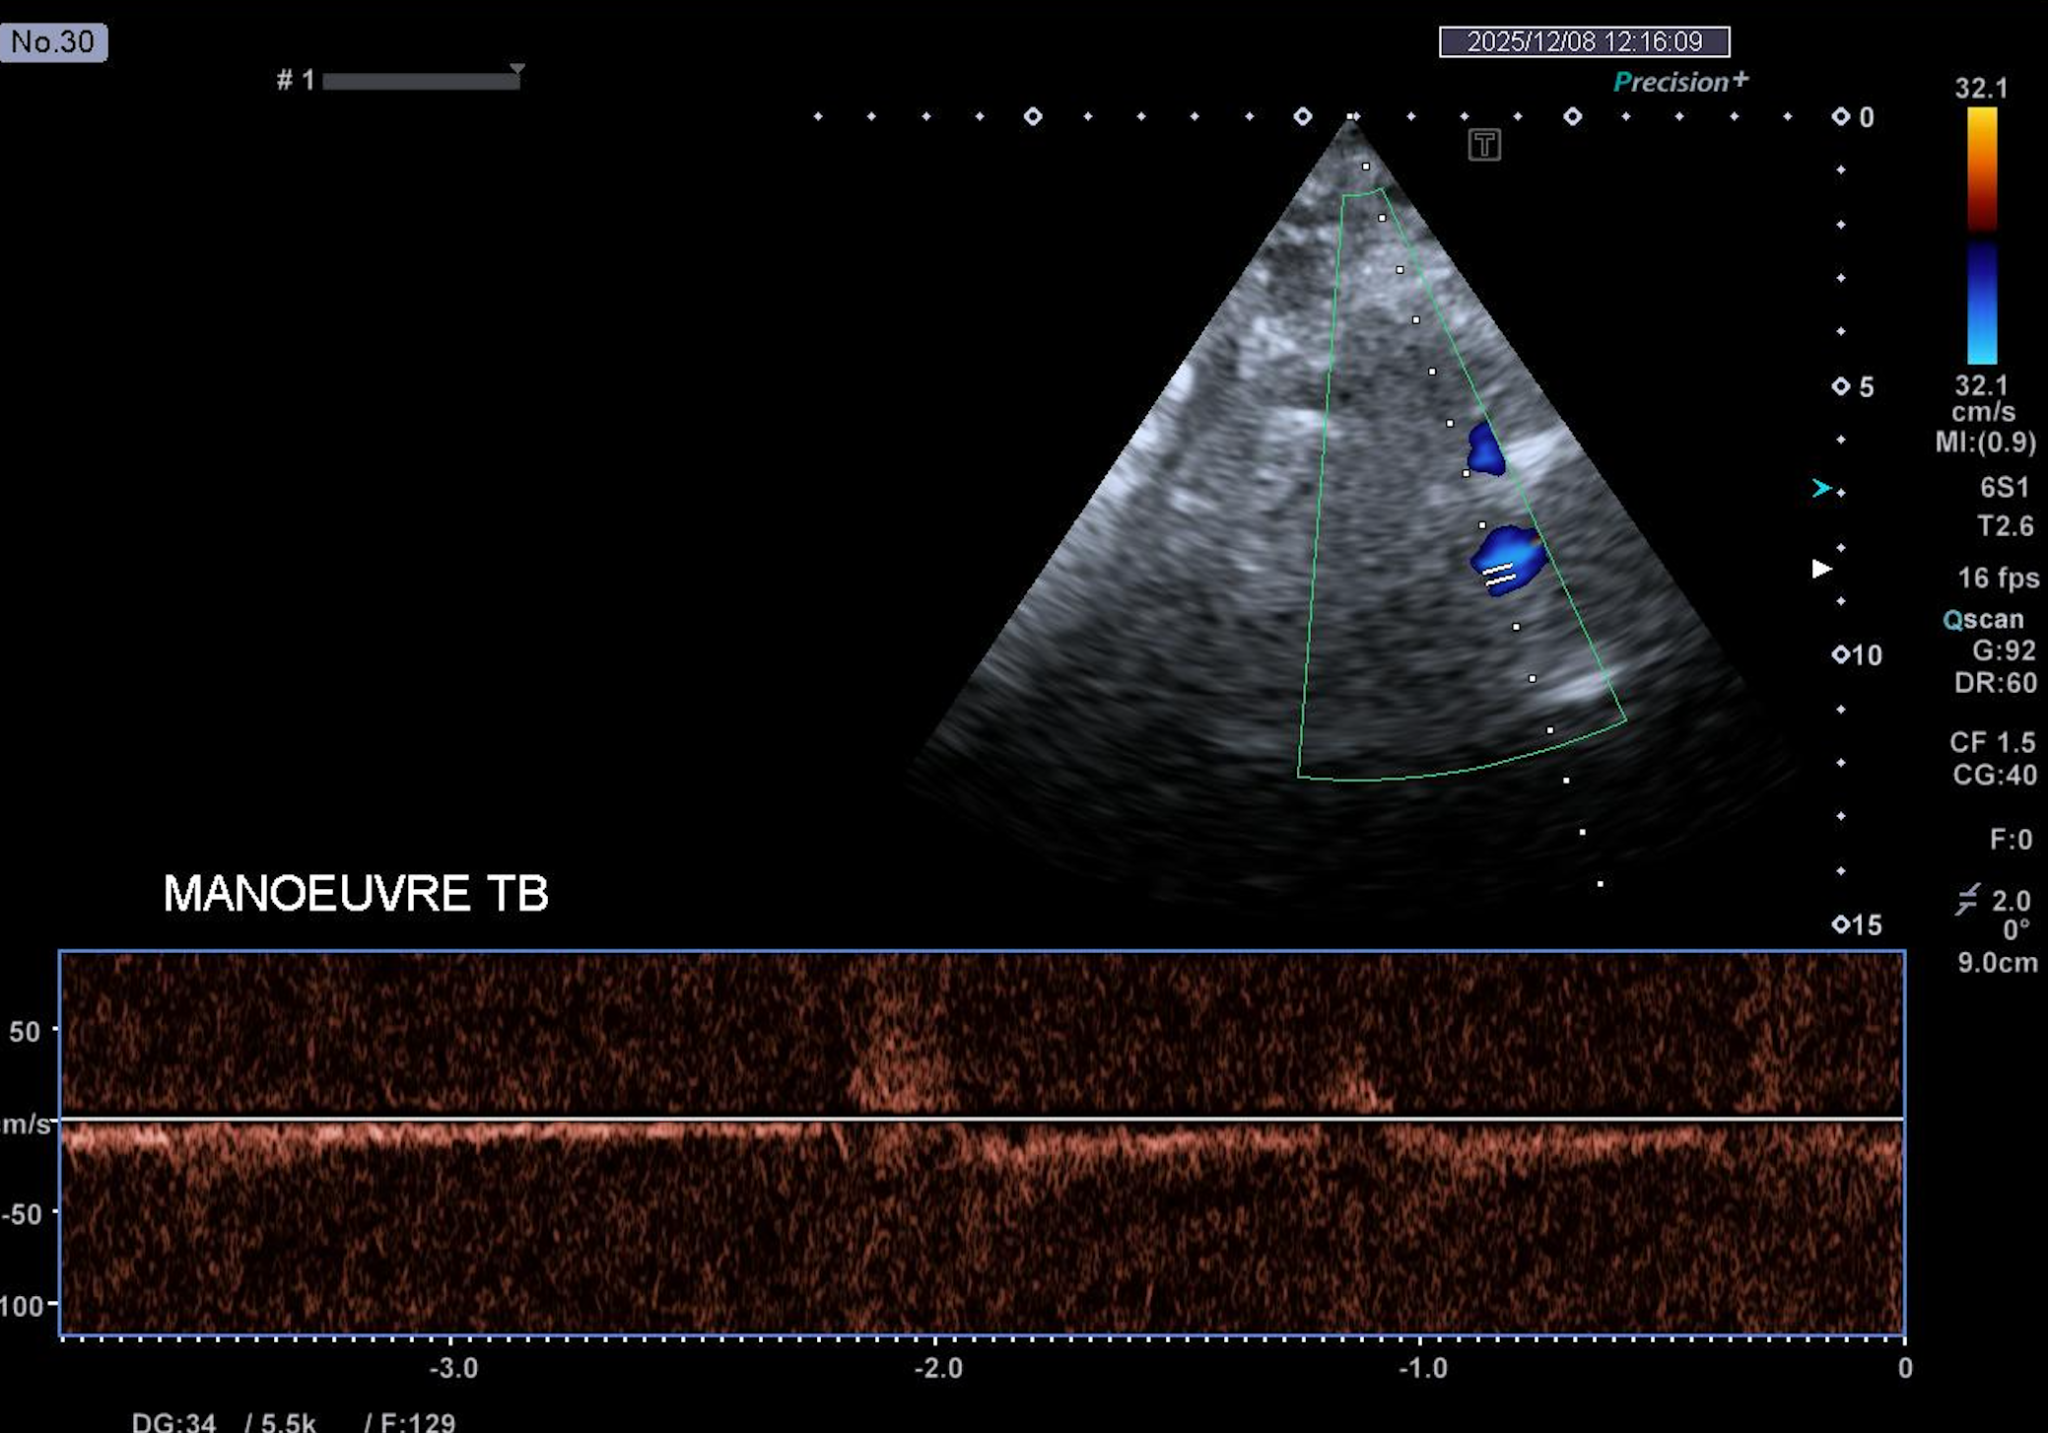

Nous réalisons une manœuvre d’hyperhémie post ischémique afin de démasquer une insuffisance vertébro basilaire à l’effort, qui est une indication opératoire.

Un brassard est donc gonflé au bras homolatérale à une pression supérieure à la tension artérielle du patient . Le patient débute alors des exercices musculaires à type de contractions répétés du poing.

Chez un sujet sain, la compression et la décompression à l’aide du brassard ne modifient pas le flux sur la vertébrale et sur le tronc basilaire.

En cas de vol, la compression à l’aide du brassard pourra normaliser le flux sur la vertébrale (les besoins en oxygène ayant diminué suite à la compression de l’artère humérale par le brassard).

A la levée du garrot, surtout après effort , le vol sera plus marqué et permettra de démasquer un vol sur le tronc basilaire.

Chez ce patient ; on retrouve un vol sur le tronc basilaire traduisant une insuffisance vertébro-basilaire à l’effort. Cette insuffisance pose l’indication opératoire, le patient est adressé au chirurgien.